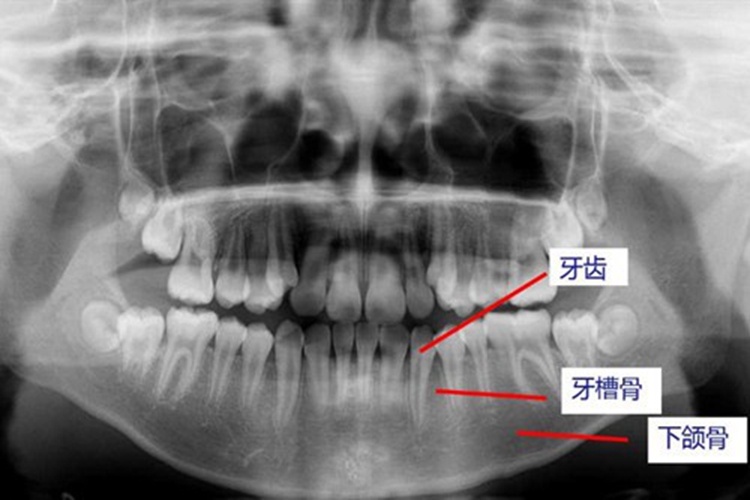

牙槽突即牙槽骨,是上下颌骨包围和支持牙根的部分,位于牙龈以下位置,从X片中可以观察到,与牙根有重叠。容纳牙根的窝称牙槽窝,在冠方牙槽窝的游离端称牙槽嵴,牙槽嵴的形态在前牙区为圆柱状,磨牙区为扁平状,而在颊舌侧变薄甚至消失。